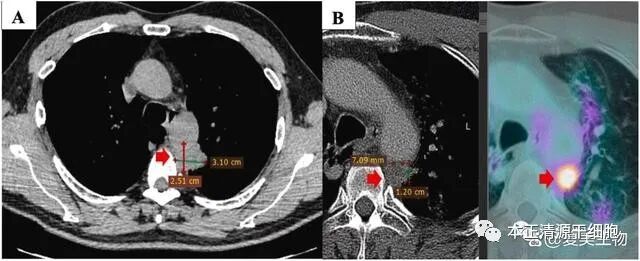

很不幸,PET/CT复查评估显示原发病灶增大到26×35mm,且SUVmax值为22.6(下图A),并且又出现了多个新发病灶。因此,患者的治疗方案不得不又要改变。

图3。联合治疗前后的原发性肿瘤。原发性肿瘤在二线治疗后进展(4个周期的阿力玛、卡铂、凯曲达)(A)。联合NK细胞治疗、吉西他滨、贝伐单抗(B)、3个月后(C)和6个月后,原发性肿瘤在治疗结束时减少(D)。